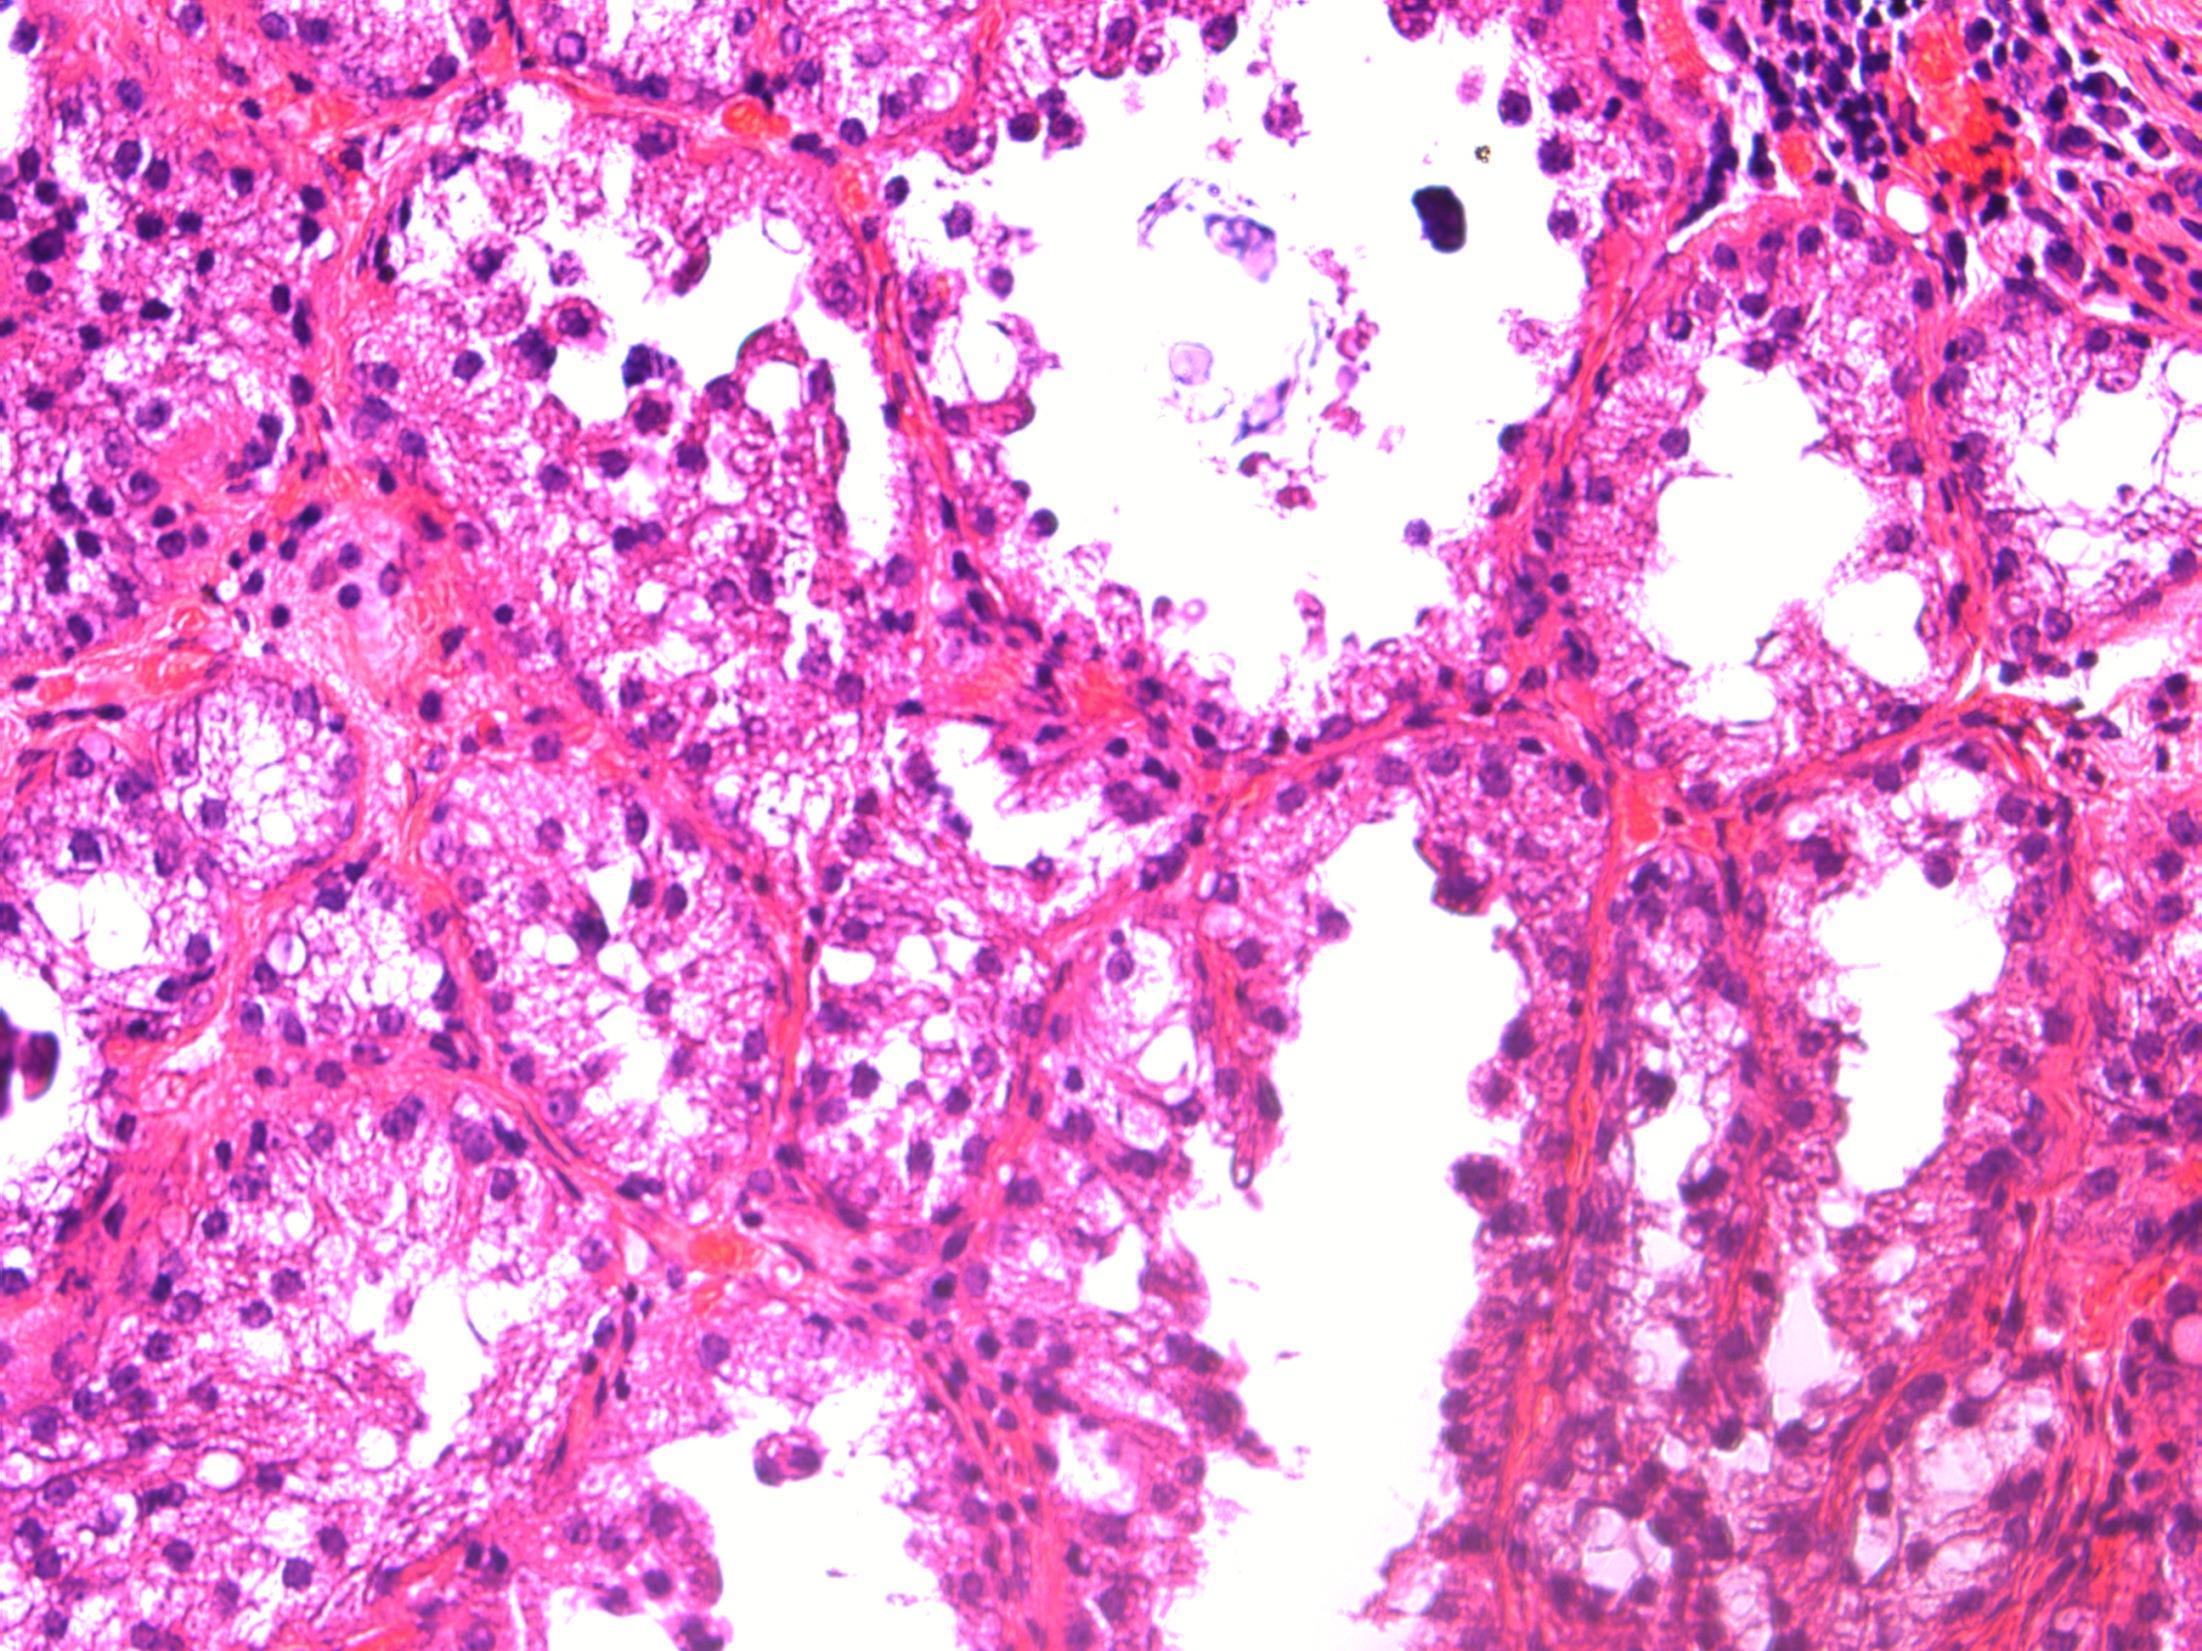

50F, Breast screening shows a 4mm area of microcalcification in lower outer right breast. Stereotactic core biopsy taken

• Breast cores – Focal lactational change with microcalcifications (B2)

Focal lactational change

Description: Dilated acini with secretions, vacuolated cytoplasm and hobnail appearance. Microcalcifications associated. No evidence of DCIS or invasive malignancy.

Diagnosis: Lactational change with microcalcifications (B2)

• Biopsied because of microcalcifications .

• Usually seen associated with pregnancy/breast-feeding, unlikley in this age as 50 years old.

• Can be seen in non-pregnant (even nulliparous) women – usually focal, no clinical significance, like in this case.

• Can have associated ADH/DCIS, not present in this case.

• No further treatment required.